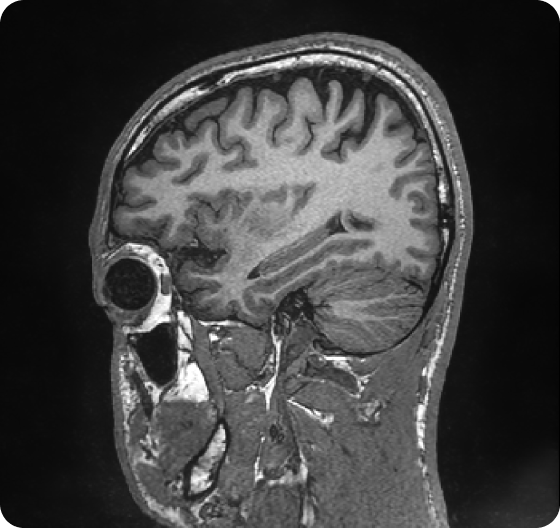

Faster scans, sharper images

SwiftMR reduces MRI scan times. SwiftSight delivers objective, replicable brain health metrics.

Standard of care

With SwiftMR